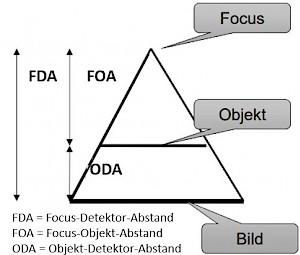

FOA = Fokus-Objekt-Abstand . - . ODA = Obkekt-Detektor-Abstand . - . FDA = Fokus-Detektor-Abstand

Da der Abstand zwischen der Haut (Objekt) an der Vorderseite des Patienten und Film( Detektor) konstant ist, wird das Verhältnis FOA:FDA (FOA = Fokus-Objekt/Haut-Abstand; FDA = Fokus-Detektor/Film-Abstand) mit zunehmendem Abstand von der Röhre kleiner. Das führt dazu, dass Röntgenaufnahmen bei großem Abstand relativ hautfreundlicher sind als Aufnahmen, die nahe bei der Röhre durchgeführt werden.